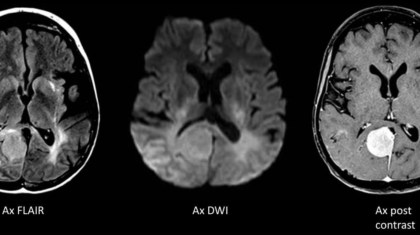

A 50 year old woman who underwent treatment for high grade pineal tumor. Presented with recurrent headache, seizures, visual disturbances and memory disturbances